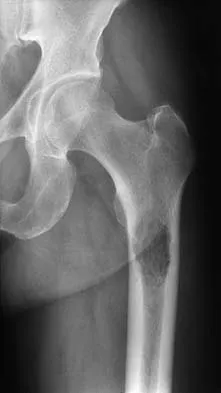

A paraplegic 32-year-old man was pulling himself up in bed by grasping the headboard rails when he felt a pop and immediate pain. A radiograph and CT scan are shown in Figures 2a and 2b. Based on these findings, management should consist of

Explanation

The coracoid process is an essential component of the superior shoulder suspensory complex and must be maintained. Open reduction and internal fixation is recommended if the fragment is large and displaced more than 1 cm. Froimson AI: Fracture of the coracoid process of the scapula. J Bone Joint Surg Am 1978;60:710-711.